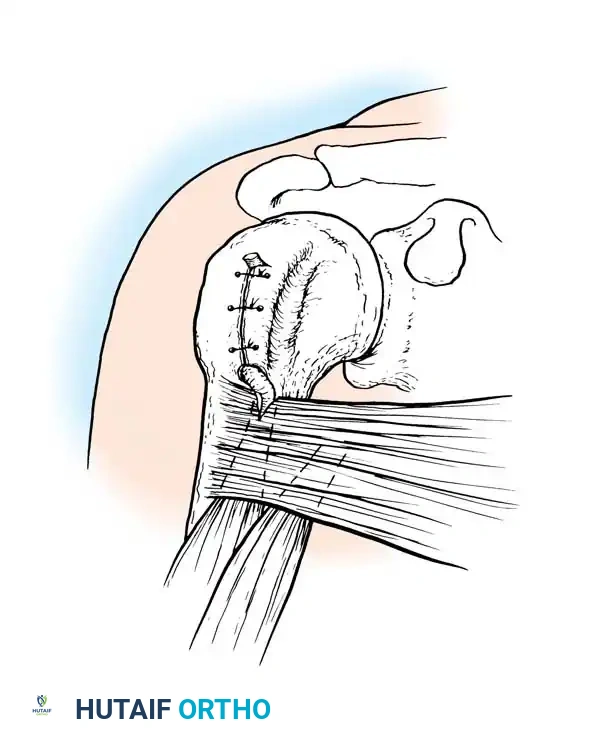

Image

Surgical exposure demonstrating the critical neurovascular boundaries during deep bursal excision.